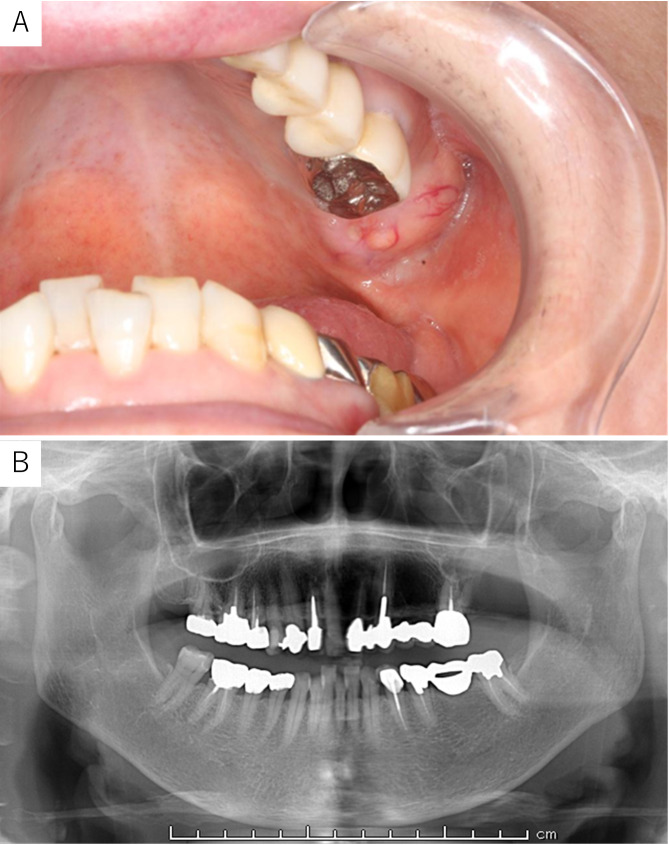

Case presentation: An 81-year-old woman was referred to our department because of swelling of the left maxillary gingiva. The left maxillary second molar had been extracted more than 10 years earlier. Surgical biopsy was performed, and histopathological findings indicated a foreign body granuloma. The patient underwent tumorectomy, during which we found a yellowish tumor. The pathologic findings were the characteristic crystal deposition, fibril-like crystals, and giant cells around the crystals. Gold hydroxamic acid staining revealed positivity for the crystals. The final pathological diagnosis was PCDD. The patient had no further symptoms and no disease recurrence.